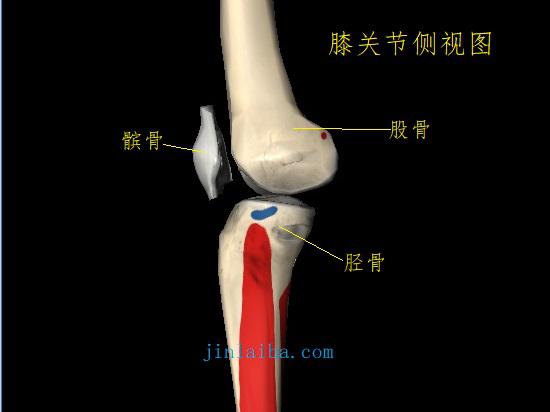

膝前疼痛是指膝关节正前方、前下方及髌骨周边的疼痛。膝前分布有多条韧带和肌腱,同时也是髌骨与股骨、胫骨相交汇的地带,无论是哪个部分出现外伤、磨损、畸形、退变,都可能会引发膝前疼痛。综合来看,可能引发膝前疼痛的常见原因如下所述(一种或多种)。

高位髌骨 高位髌骨是指髌骨在膝关节屈伸动作中的位置偏高,使其不能沿正常的轨迹滑动,并因为力线畸变而使髌骨出现额外的负载、磨损及多种应力反应。高位髌骨的主要症状就是膝关节活动受限、疼痛,可能与韧带松弛、胫骨结节病、髌骨支持带损伤等原因有关。